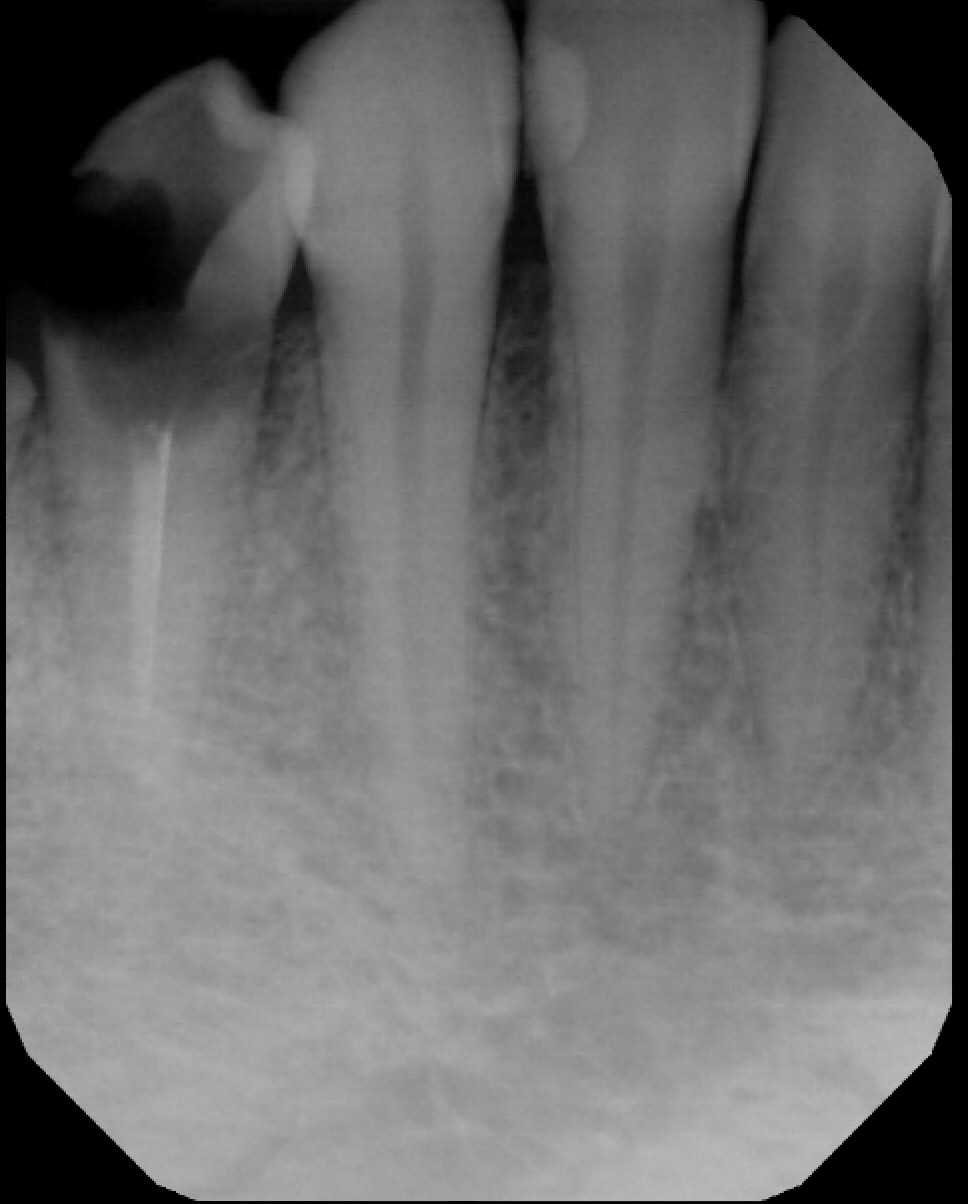

IX. RADIOGRAPHS

Note: 11 (US # 8) and 21 (US # 9) have caries into the pulp and peri apical lesions

• Caries: 13 M (D) (US # 6), 12 D (D) (US # 7), 11 M (D) (US # 8), 21 M/D (D) (US # 9), 42 M (E) (US # 26), 43 M (E) (US # 27)

• Periapical lesion on 11 (US # 8) and 21 (US # 9): correlates with the clinical finding of eroded teeth down to the dentin (almost the dentino-pulp junction)

• Conclusion: The radiolucencies seen at the apex of 11 and 21 (US # 8 and 9) were not periapical lesions. I retook a PA with a different angle (see next slide)

• Additional radiographs

Note: No periapical lesion is noted on 11 and 21 (US # 8 and 9).